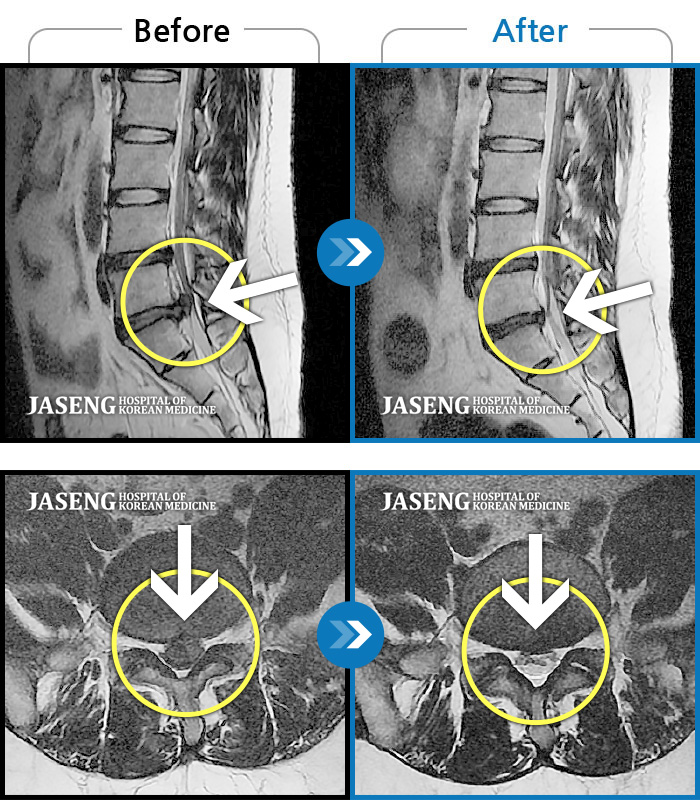

처음 내원 시 허리와 좌측 골반이 많이 아프고, 좌측 다리로 저림과 감각 저하가 있어서 보행이 원활하지 못했으며, 야간통으로 잠도 못 자고 통증 심하여 정상적인 활동이 힘든 상태셨습니다.

촬영시기

2023.09.16 ~ 2024.09.24

2024.10.04